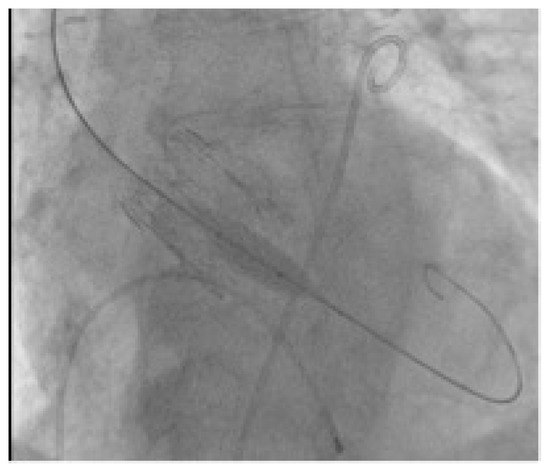

2.2. Technology

2.3. VIV-TAVR Planning and Technical Procedures